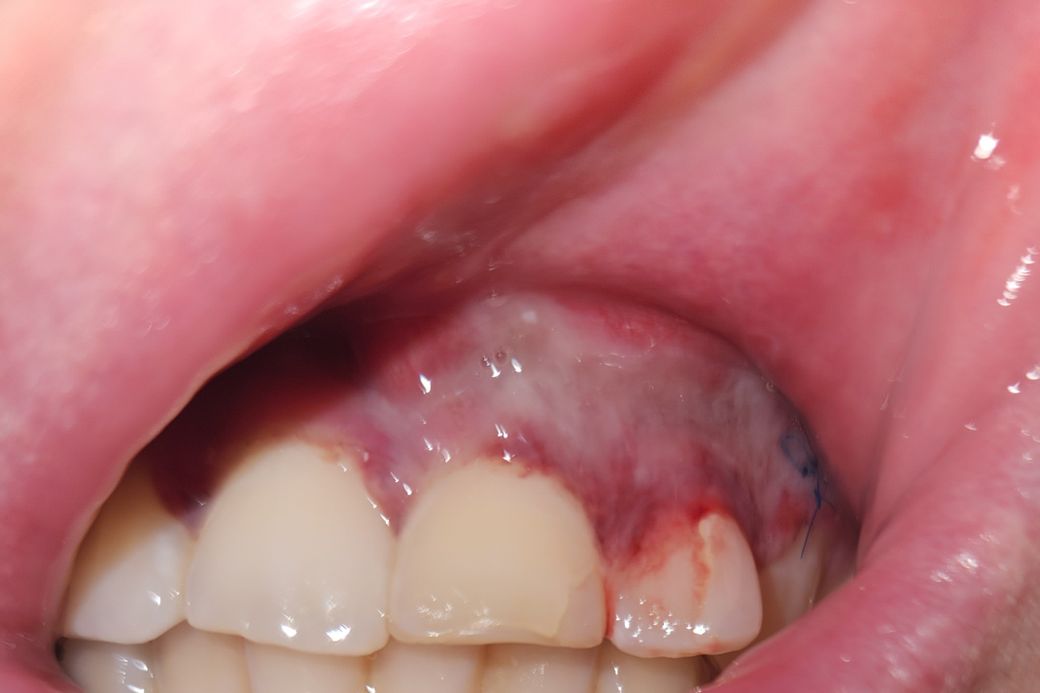

치근단 절단 수술 후 잇몸 회색으로 변색

금요일에 잇몸 낭종 때문에 시경치료, 낭종 제거, 치근단 절단, 뼈이식 수술 받았습니다.

잇몸 색이 회색인데 정상인 건지 궁금합니다.

사진으로만 봤을 경우에는 수술한 부위에 실밥이 있는 것으로 보입니다.

대부분 잇몸은 수술 후에 2주 정도가 지나면 아물게 되며 자세한 확인을 위해서 치과에서 진료를 받아 보세요